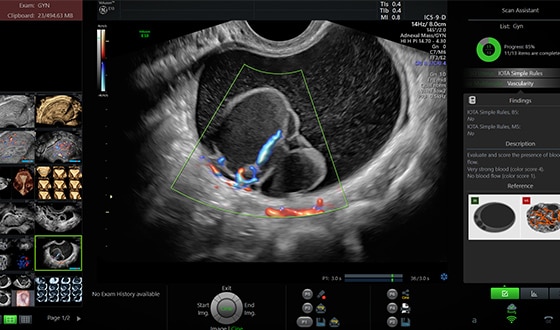

Scan Assistant

Помощник сканирования Scan Assistant — индивидуально настраиваемый протокол ультразвукового исследования пациентов. Инструмент, позволяющий стандартизировать исследования и проводить документирование данных пациентов согласно актуальным требованиям к ультразвуковому протоколу.